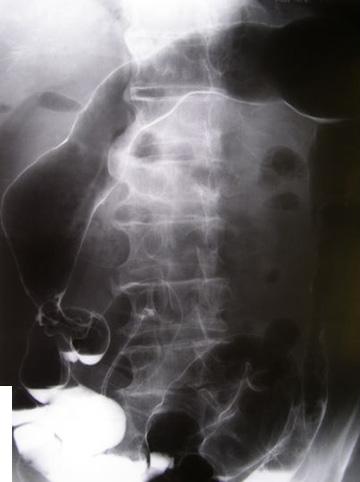

질환(병리주체)의 분류 악성 상피성종양/점액암

검사방법 X-P